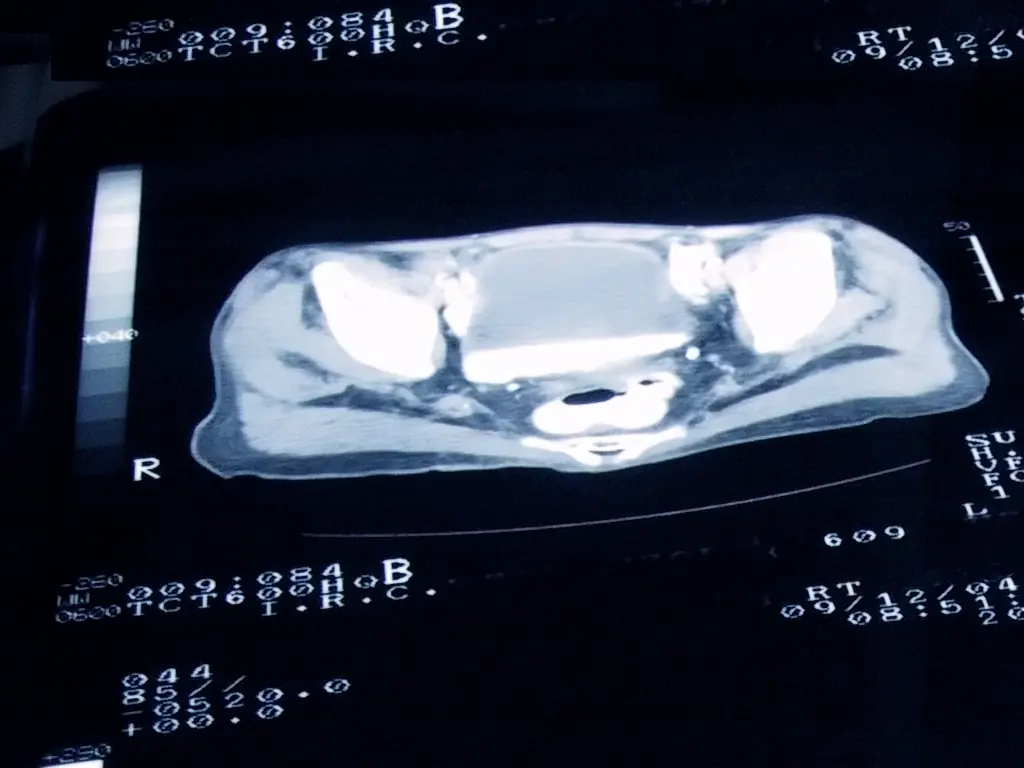

“Prostate cancer may present as a prostate nodule (hard feeling area on the prostate) or elevated PSA test, and often results in ordering an MRI and prostate biopsy,” Dr. Herbert Lepor, a urologist at NYU Langone, explained to CBS News.